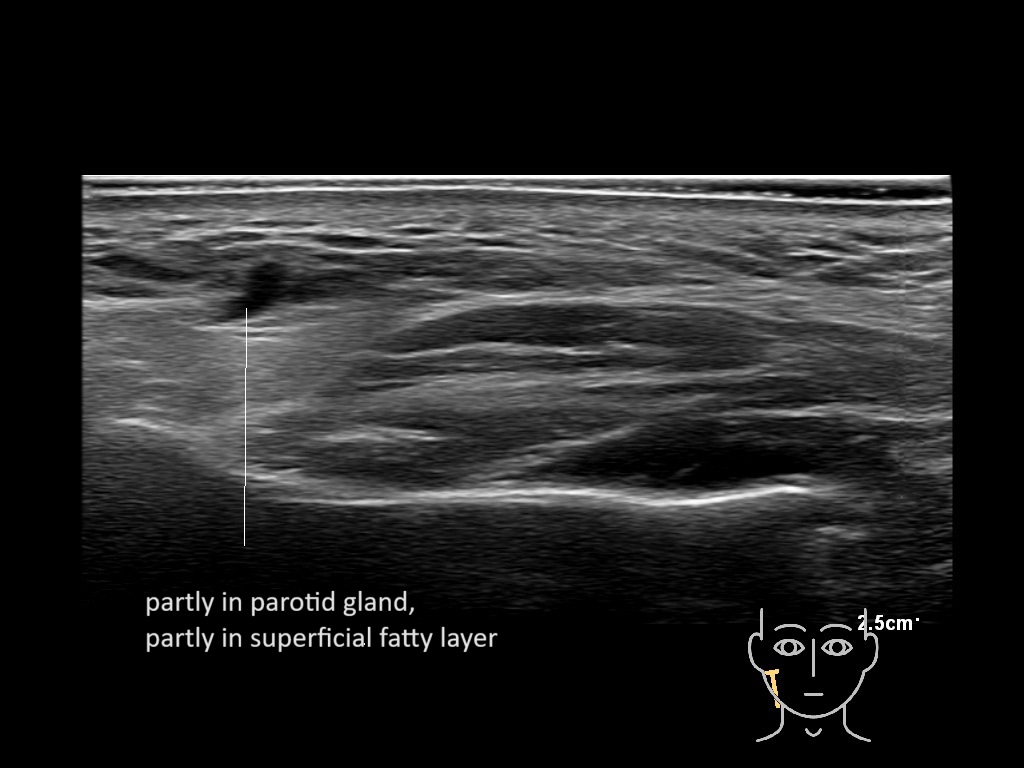

Parotid

Filler injections in the parotid gland may go unnoticed, however, inflammatory reactions and abscesses may occur. Hypervascularity can be seen with color doppler. Filler deposits are supposed to be injected into the superficial fatty layer . The space to inject into this layer may be limited. Routinely we measure a width of 2-4 millimeters with sometimes subcutaneous layers being less than one millimeter thick.

Study the first image to recognize the different layers. If you are sure about the layers, swipe to the second image to view the answer (if applicable).